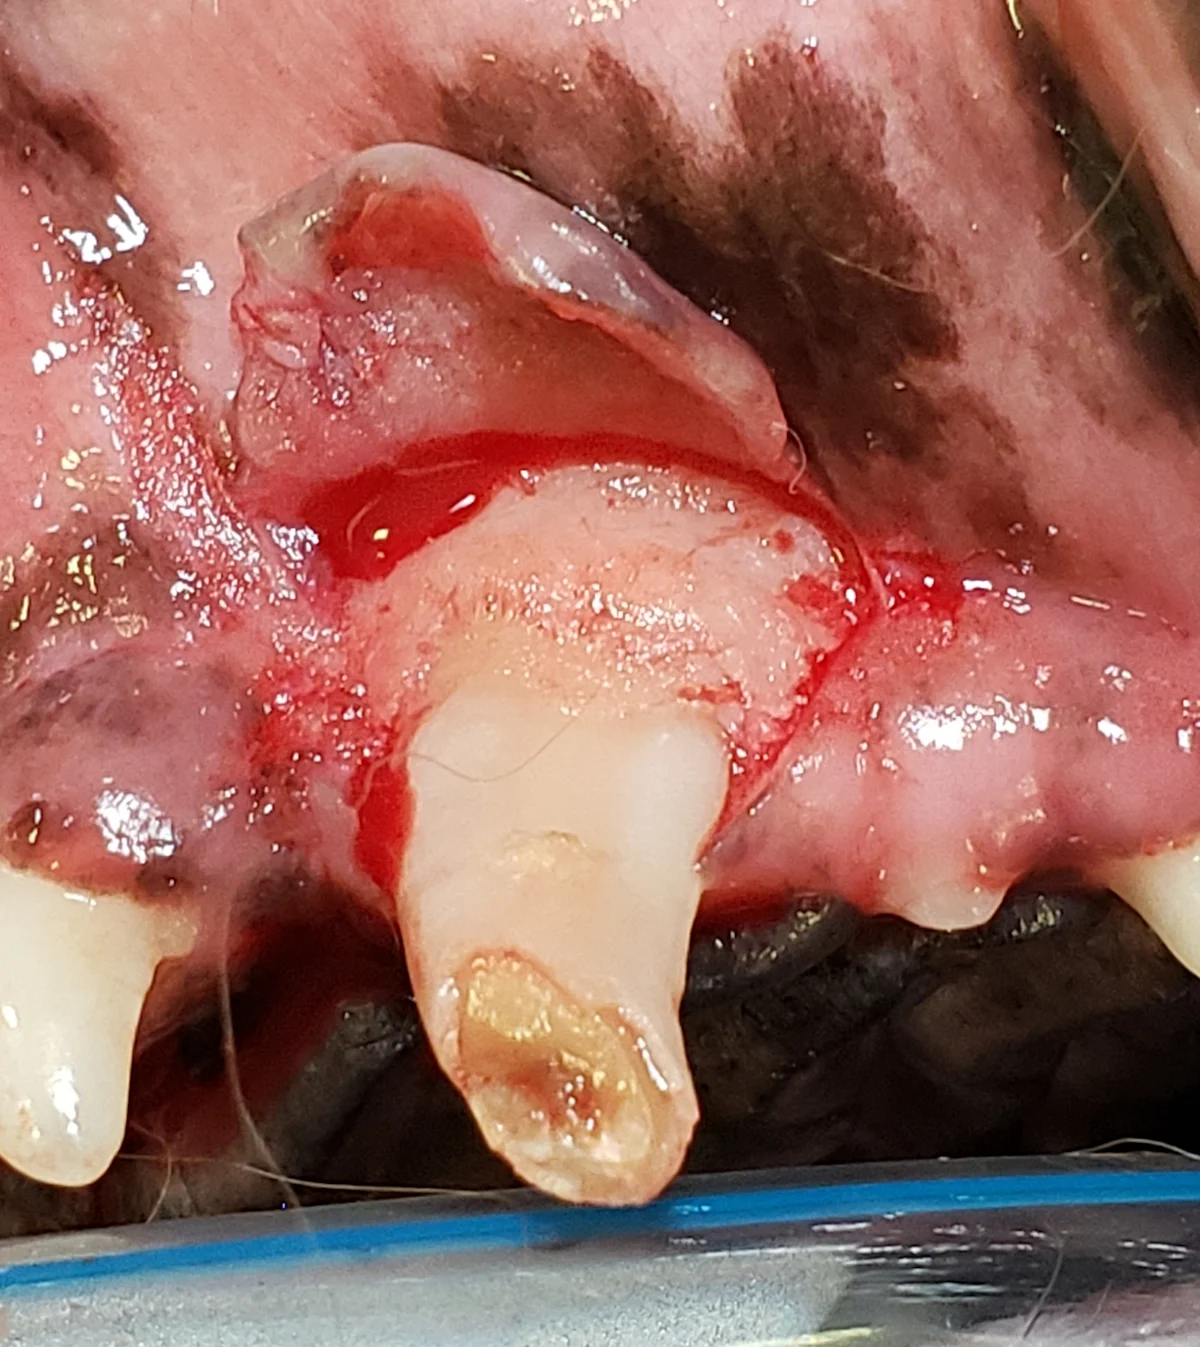

When the tooth is sufficiently loose, grasp the crown near the base (ie, neck) with small-breed extraction forceps. Gently rotate the tooth around its axis in one direction, hold, then rotate it in the other direction. Do not rotate the apex into the nasal cavity. If there is resistance, determine where the tooth needs additional bone removal or elevation (A). If the tooth can be easily removed with a pulling force, fully extract the tooth (B).

A